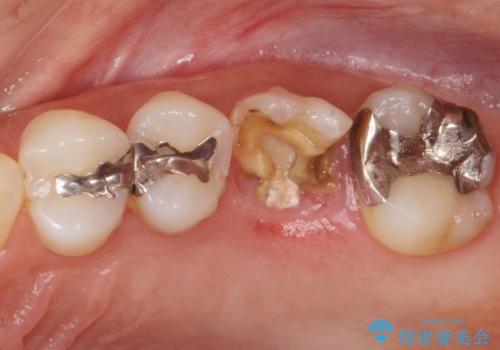

[歯の破折] インプラント埋入を行うための大規模骨造成